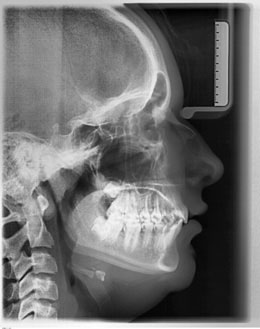

• Correction of upper protrusion (X-ray view)